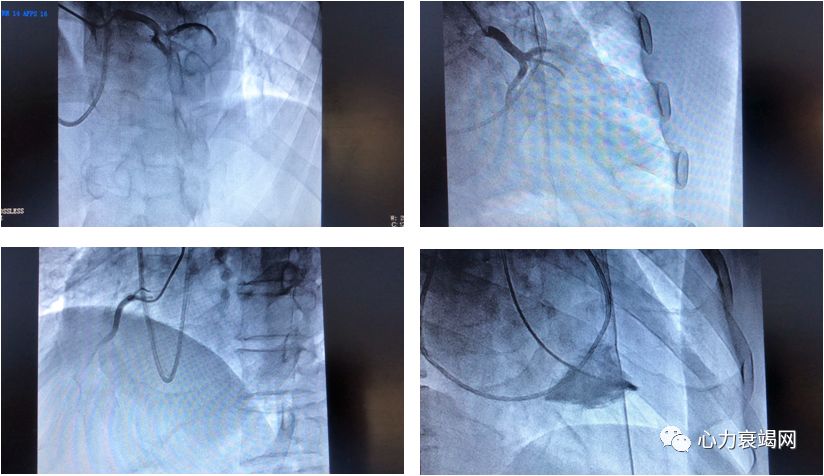

酒精消融术

疑诊的患者完善多普勒二维超声心动图,心脏MRI,左室造影检查

怀疑冠心病时行冠脉造影

血流动力学检查对指导临床治疗非常重要